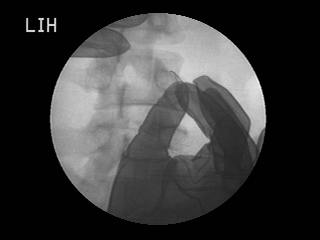

– 오십견으로 어깨 관절이 심하게 굳어 있을 때 (수압팽창술) 어깨 통증이 심하고 팔이 안 올라가는 경우 어깨 관절이 염증으로 좁아져 있는 상태입니다. 이 때 C-arm 기계를 이용하여 좁아진 어깨 관절낭 부위를 직접 확인하고 관절강을 넓히고 염증을 줄이는 치료를 할 수 있습니다. 그 밖에도 고관절, 천장관절통 등 여러부위에서 C-arm 기계를 이용한 치료가 가능합니다.